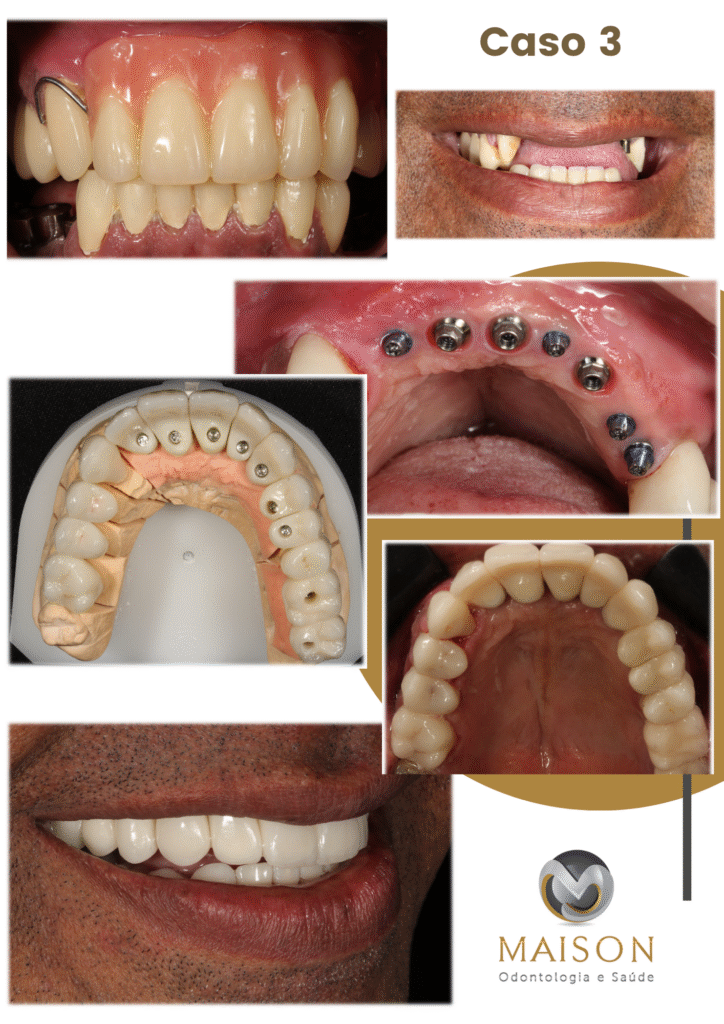

Transformação do Sorriso

Veja o que Nossos Pacientes

25 Anos de Experiência

Transformando Sorrisos

Com mais de 25 anos de experiência na área odontológica, o Dr. Giancarlo, Dra Morgana e equipe se destacam como um profissionais altamente qualificados e comprometidos com a saúde bucal de seus pacientes. Reconhecidos por sua abordagem cuidadosa e profissionalismo exemplar, eles se tornaram referência na área por oferecer tratamentos eficazes e humanizados.

- Técnicas Avançadas de Reabilitação Oral: Implantes Unitários, Múltiplos, Overdenture, Protocolo, Técnica Facco no osso Zigomático; realizamos todos o tipos de próteses sobre implante.